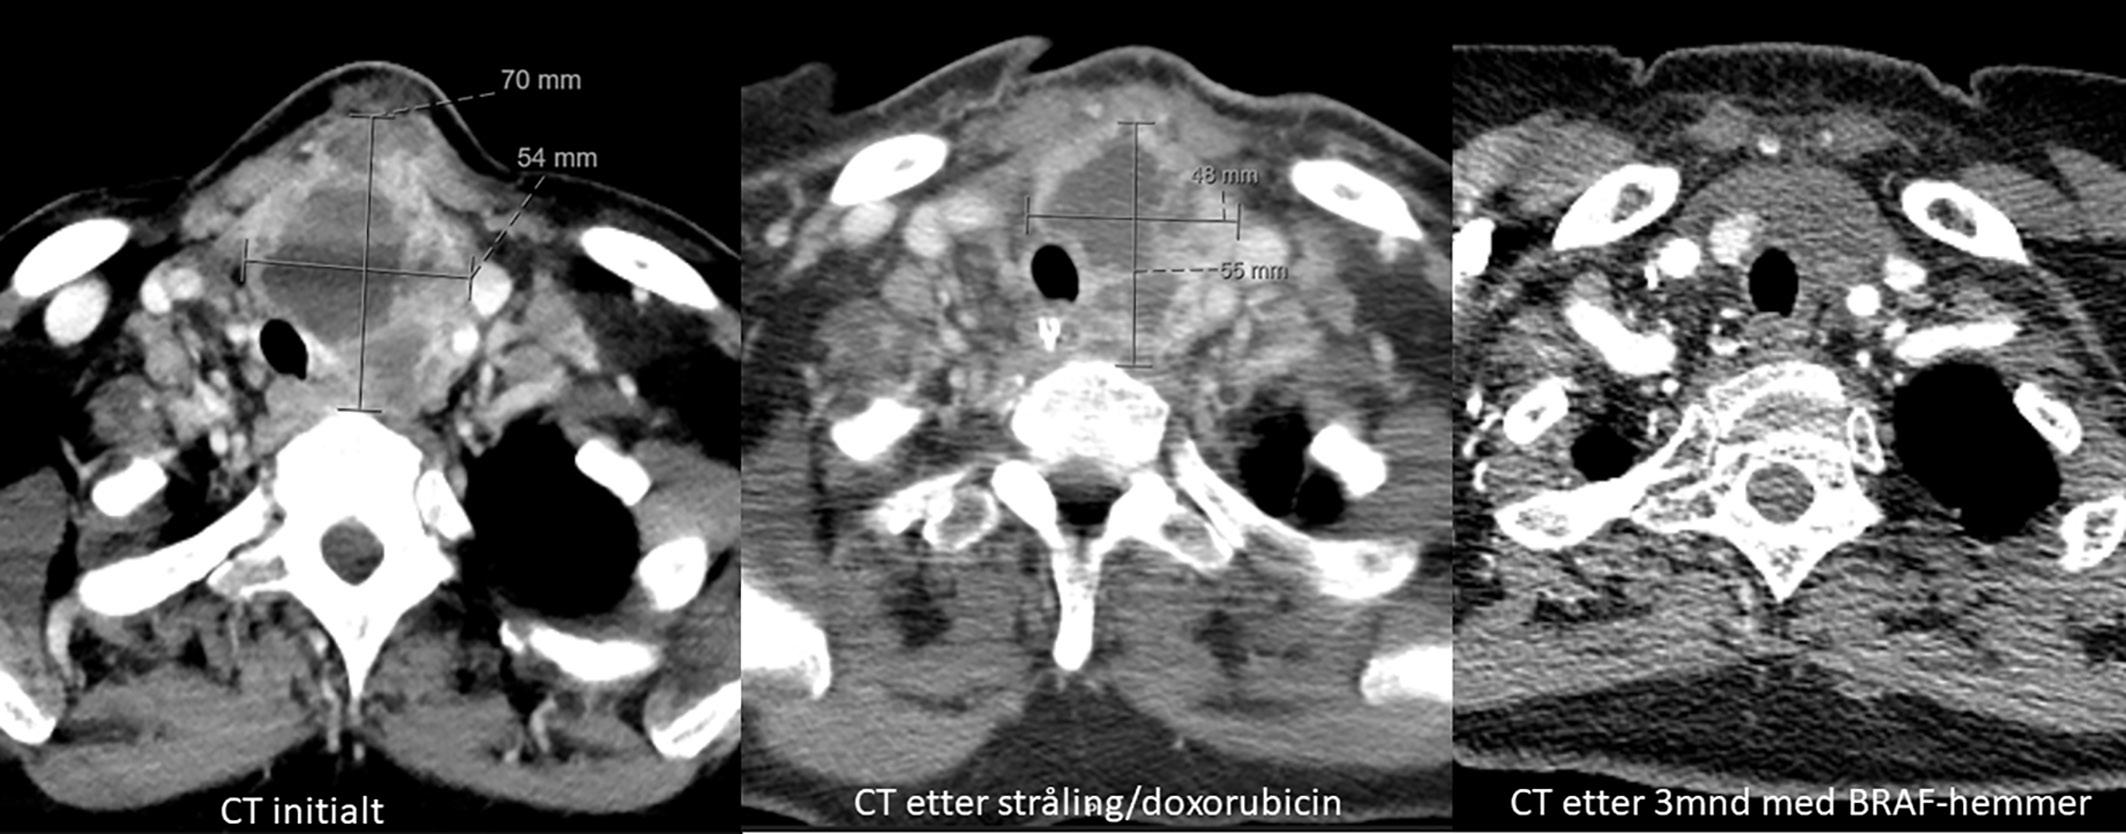

BILDE 1: Initial CT collum viste tumorstørrelse på 70x54 mm. CT undersøkelse en måned senere som var tre dager etter fullført strålebehandling viste tumor-reduksjon til 55x48mm. CT undersøkelse etter ytterligere tre måneder med tillegg av dabrafenib og trametinib viste at tumor hadde gått tilbake til tre cm i størrelse. Samtykke til publisering av røntgenbildene er innhentet fra pasientens ektemann da pasienten er død.

KASUISTIKK 1

En 72 år gammel kvinne oppsøkte fastlegen med nyoppstått 2x2 cm stor kul på halsen. Hun ble henvist til ultralydundersøkelse lokalt og senere ble det utført finnålsprøve samme sted, som ga mistanke om anaplastisk karsinom. Da hadde svulsten vokst til 8 cm. Hun ble henvist til regionsykehus og innlagt neste dag. Grovnålsbiopsier bekreftet anaplastisk thyreoideakarsinom. Pasienten hadde da utviklet heshet og smerter, men hadde ikke svelgvansker eller dyspné. Tumor i thyroidea var inoperabel, samt at hun hadde multiple små lungemetastaser. Det ble startet med strålebehandling to ganger daglig (1,5 GYx30-45) samt ukedose doksorubicin. Behandlingsrespons ble evaluert med CT-undersøkelse (Bilde 1). Det ble påvist BRAF (V600E) mutasjon, og etter fullført strålebehandling ble det startet med BRAF-/MEK hemmerne dabrafenib 75 mg x 1 og trametinib 1 mg x 1 en måned etter innleggelsen. Dosen ble økt etter ni dager. Tumor og metastaser på hals og i lunger viste komplett respons, og pasienten ble operert med venstresidig hemithyreoidektomi etter fem måneder. Det var betydelige adheranser og forandringer rundt thyroidea relatert til tidligere behandling. Endelig histologi viste kun enkeltliggende tumorceller i thyreoidealappen. Dabrafenib 100 mg x 2 og trametinib 2 mg x1 ble kontinuert med enkelte pauser på en til tre uker på grunn av nøytropen feber.

CT thorax/abdomen/bekken 16 måneder etter sykdomsdebut viste ingen tegn til persisterende sykdom. Imidlertid hadde pasienten fått smerter i skulder og 17 måneder etter sykdomsdebut ble det påvist en 4,5 cm stor metas-